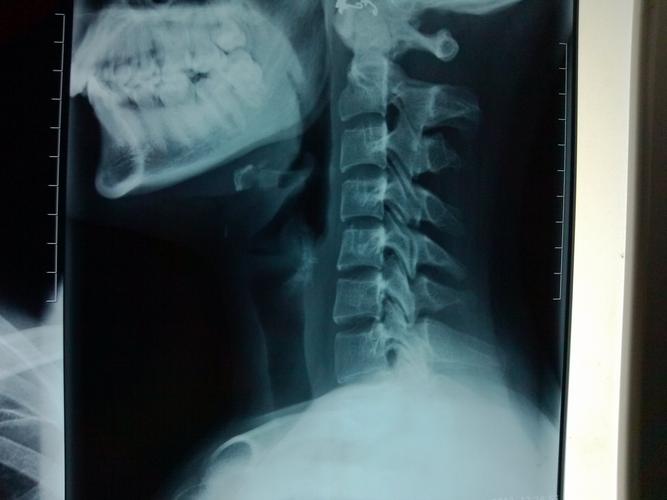

颈椎DR多久后可以备孕

颈椎DR多久后可以备孕,这是现在很多人都关心的一个问题。颈椎的影响想必每一个想要宝宝的女性朋友们都深有体会。颈椎的影响也是挺深远的,那么就赶紧了脚步小心,不要那么轻易的备孕。那么小编今天就带大家去了解一下,避免颈椎DR多久后可以备孕。